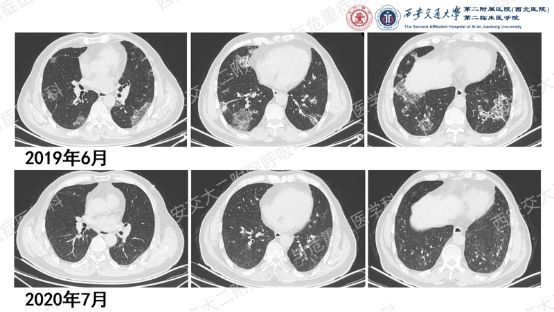

该患者确诊后,按体重给予50mg(0.75mg/kg)强的松晨起顿服,1月后复查胸部CT提示肺部阴影吸收好转,随后调整剂量为40mg/d,之后以 “每月顿服量减1片”的速度逐步减量,减至10mg/d维持3月,又减至5mg/d维持3月,总疗程13个月。治疗期间定期监测血压、血糖、电解质,未出现明显激素相关不良反应;最终复查胸部影像学示病灶基本吸收